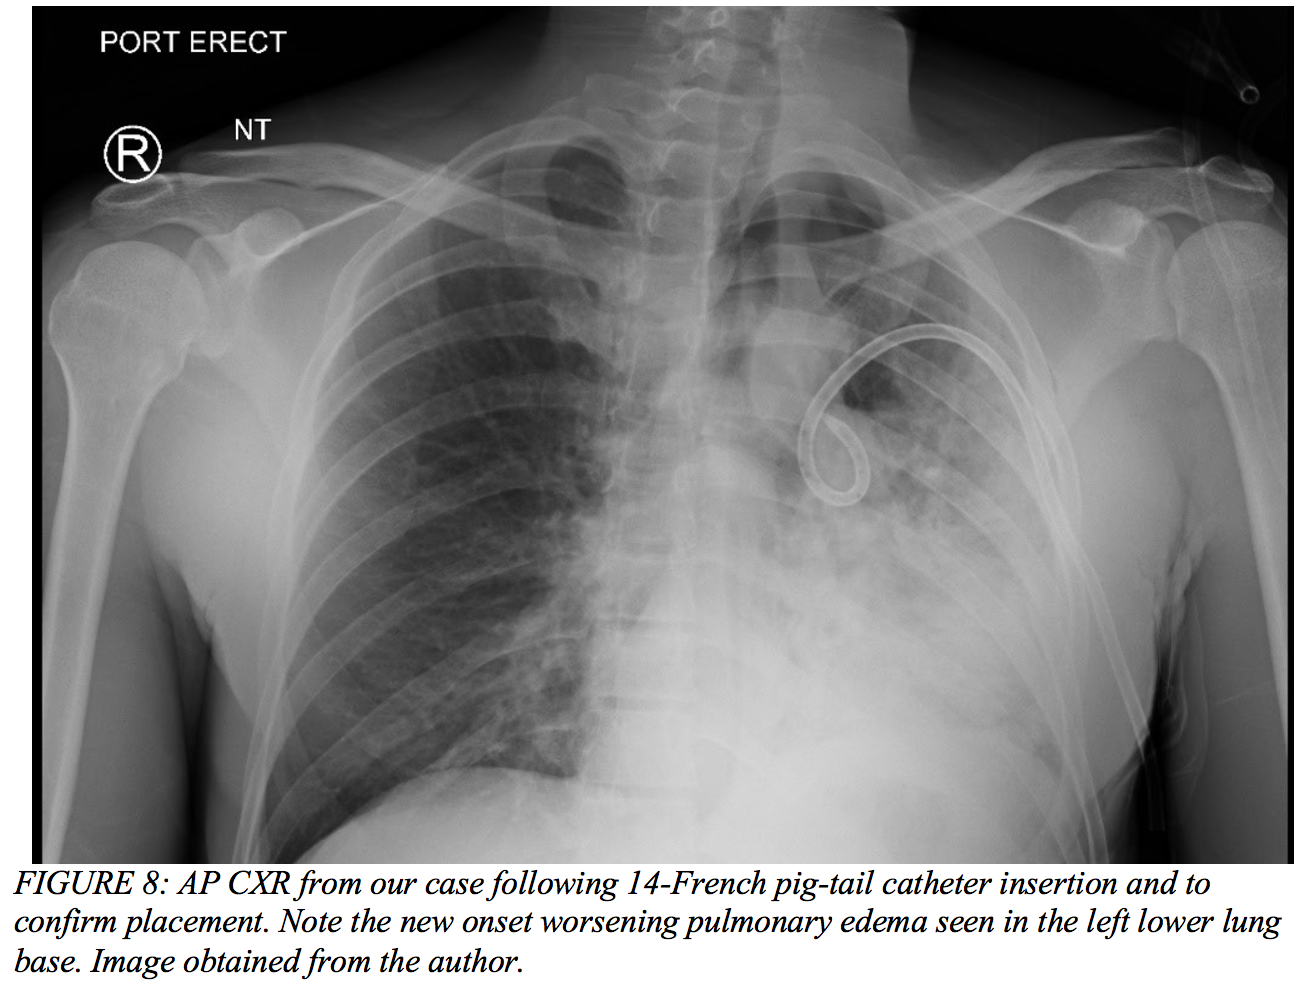

- Be aware of re-expansion pulmonary edema that typically occurs following chest tube placement. This is particularly the case in patients that may have had a small subacute asymptomatic pneumothorax for more than one or two days.1

Case Conclusion

After initial imaging displayed a pneumothorax (Figure 7 above), our 39-year-old male had a pig-tail catheter placed successfully (Figure 8 below). However, his dyspnea failed to improve, and he continued to desaturate even when connected to supplemental oxygen via non-rebreather. The decision was made to replace the pig-tail catheter for a 28-French chest tube (Figure 9). His clinical status failed to improve even after this intervention, and he ultimately required intubation due to impending respiratory failure and an evolving pulmonary contusion. The patient was then transferred to the surgical intensive care unit and closely monitored on mechanical ventilation for two weeks. His oxygenation and ventilation improved over time, and he was extubated and subsequently discharged without any further complications.